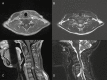

Ependymomas are rare primary central nervous system (CNS) tumors in adults. They occur most commonly in the spinal cord, and have classically been graded histologically into World Health Organization (WHO) grades I, II, or III based on the level of anaplasia. Recent data are showing that genetic heterogeneity occurs within the same histological subgroup and that ependymomas arising from different CNS locations have different molecular signatures. This has renewed interest in developing targeting therapies based on molecular profiles especially given the variable outcomes with radiation and the poor results with cytotoxic agents. In this paper, we present the case of a 46-year-old woman with a classic presentation of spinal cord ependymoma and discuss the current histopathological and molecular classification for ependymomas as well as current guidelines for patient management.